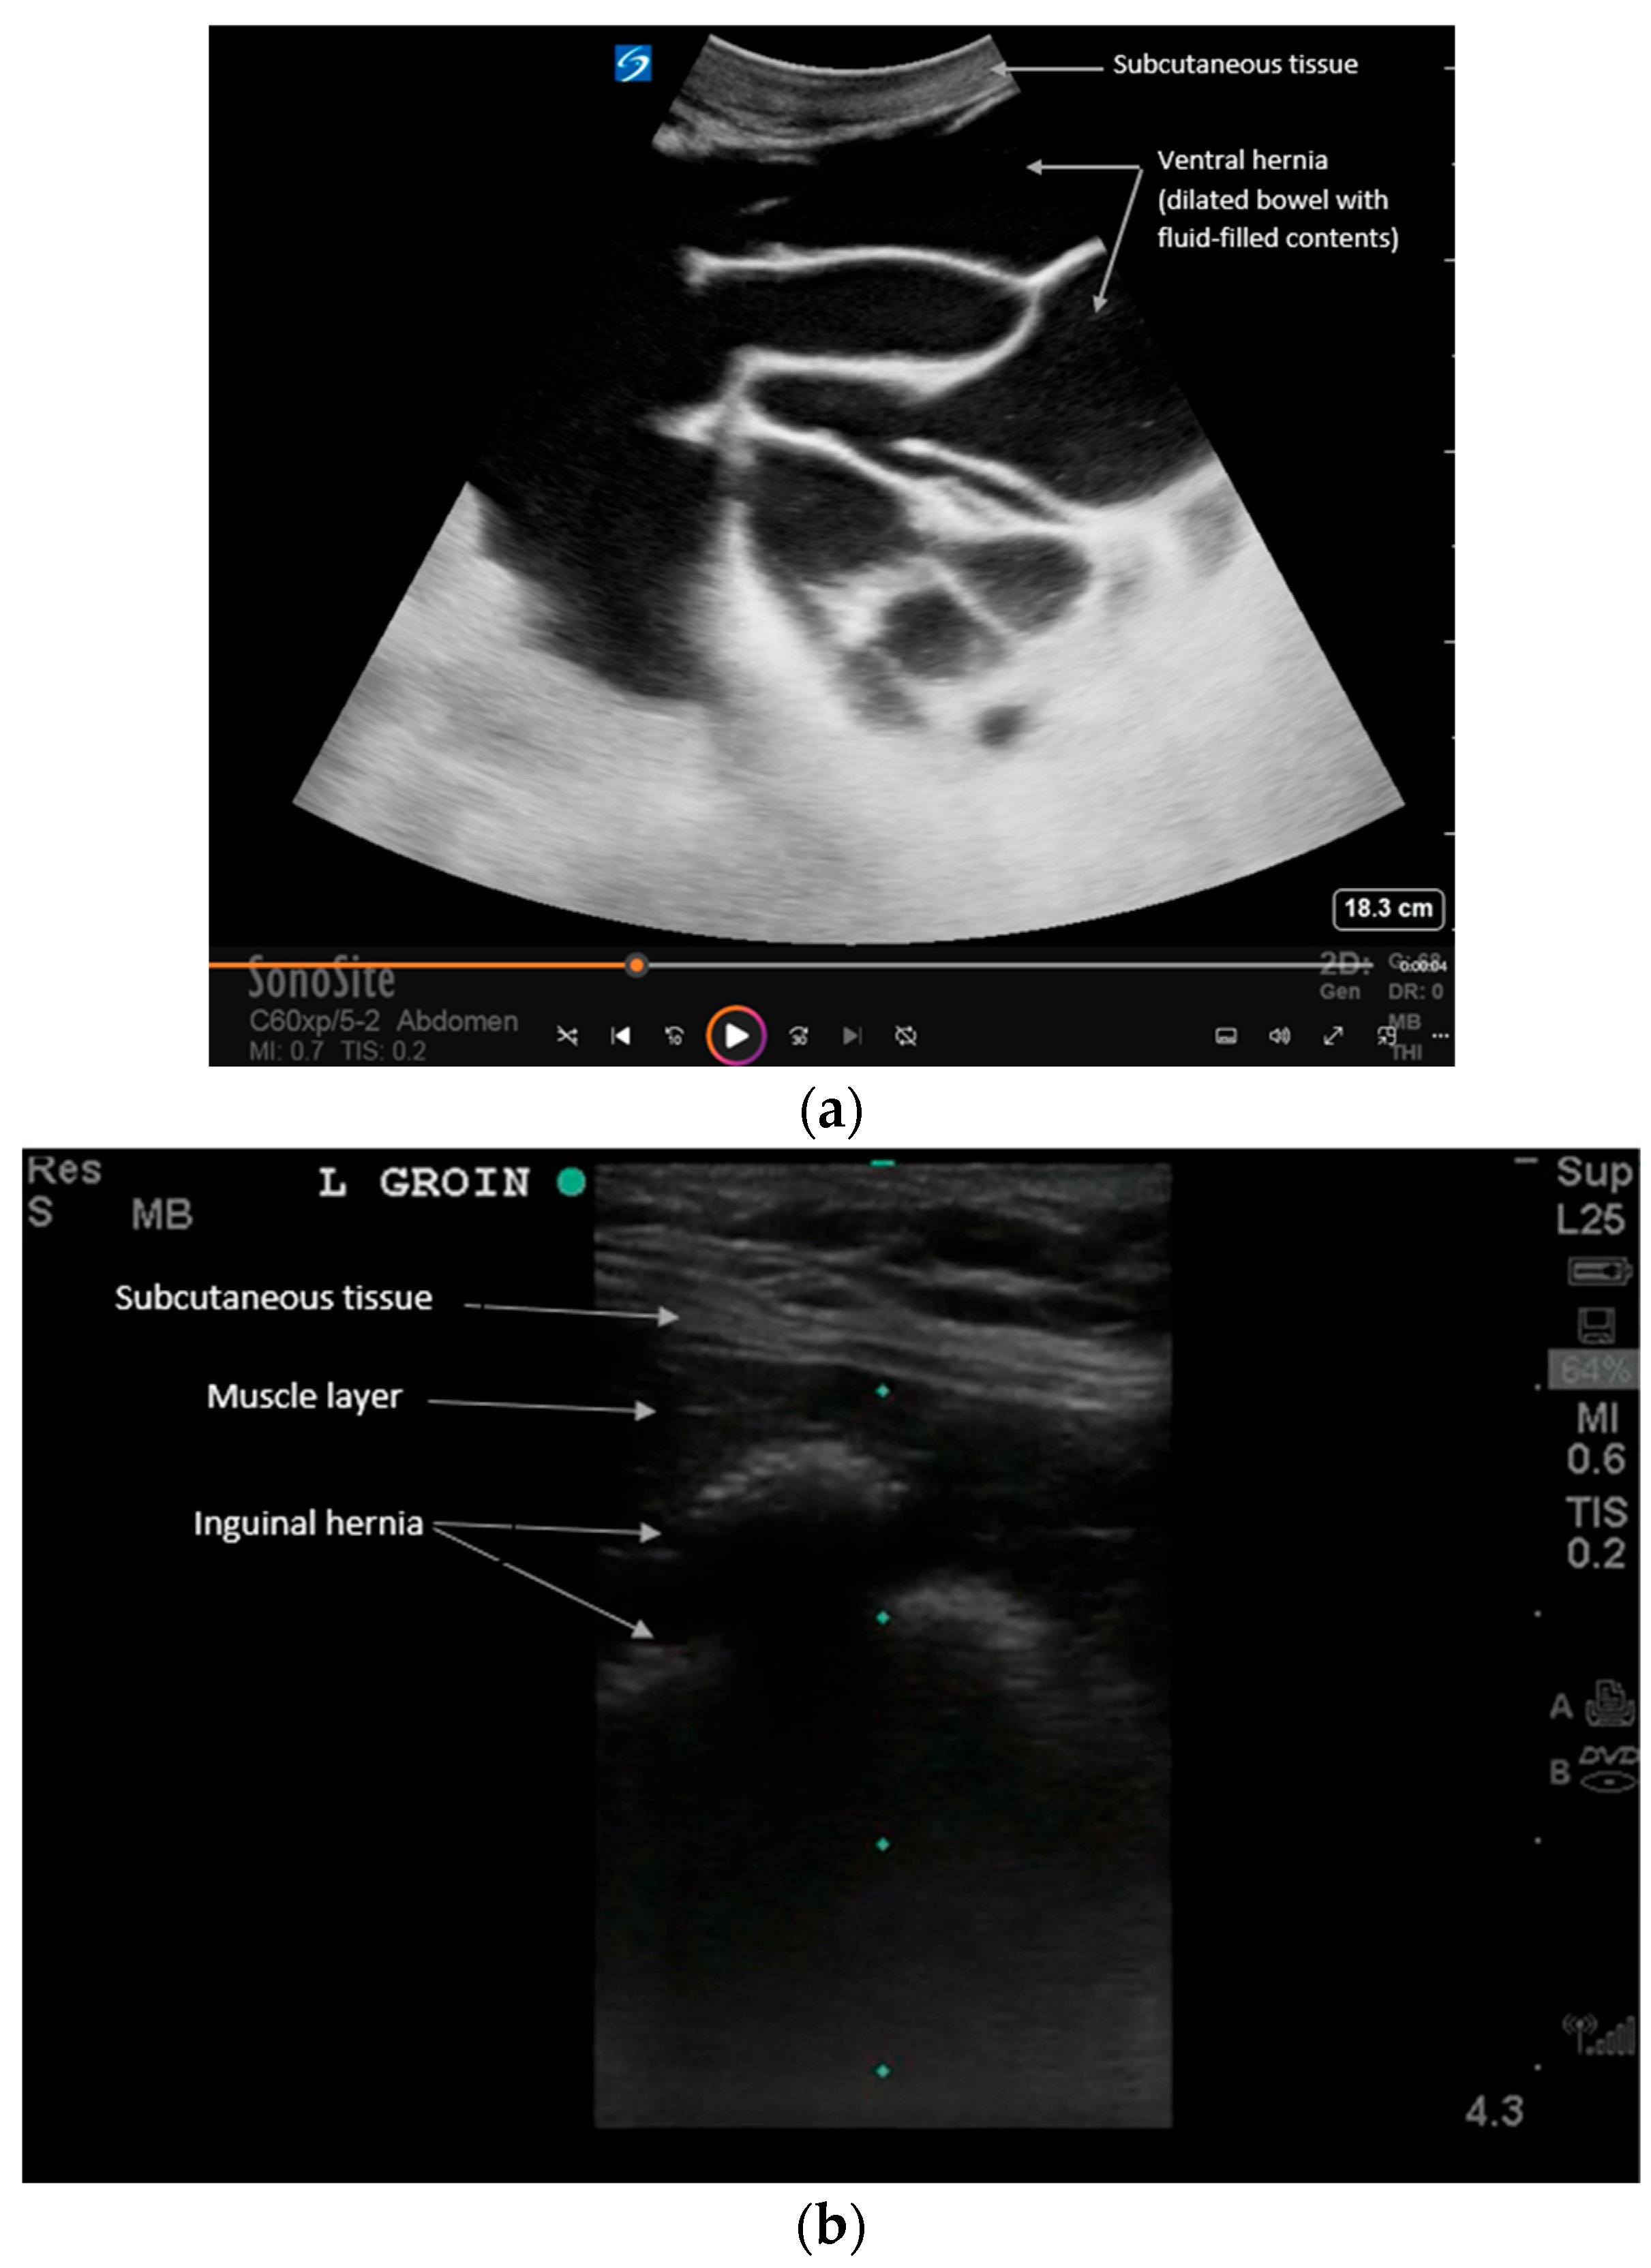

Examples of (a) ventral and (b) inguinal hernias that contain loops of bowel on POCUS. See Supplementary Videos S2 and S3 for examples of dynamic findings. Intestinal hernias can be evaluated with ultrasound at the bedside for faster recognition and manual reduction. Ultrasound reveals loops of bowel traversing the abdominal wall muscles. Dynamic assessment with Valsalva is recommended per expert consensus to evaluate reducibility and complications [11]. For example, the patient can be asked to perform a Valsalva maneuver to exaggerate the hernia during real-time ultrasound. Increased vascular flow, extra-luminal fluid, bowel dilation, or wall thickening can all suggest an increased risk for hernia incarceration or strangulation, which requires expedited treatment. Also, the lack of peristalsis within the bowel is a sign of complication [18].